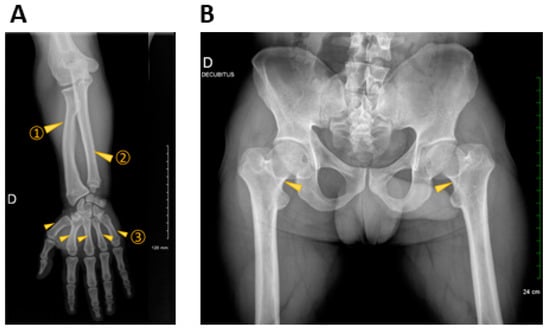

| Other clinical features | Shortening of limbs | Short limbs, continuous growth retardation | Short limbs (especially upper limbs), bowing legs | Shortening of limbs (rhizomelia and mesomelia), continuous growth retardation |

| Radiologic findings | Shortening and thickening of femora and tibia, metaphyseal flaring of distal femora and proximal tibia | Multiple skeletal abnormalities | Metaphyseal flaring of distal femora and proximal tibiae | Multiple spinal abnormalities |

| Diagnosis | Hypochondroplasia or mild achondroplasia | Achondroplasia or severe hypochondroplasia | Hypochondroplasia | Achondroplasia or severe hypochondroplasia |